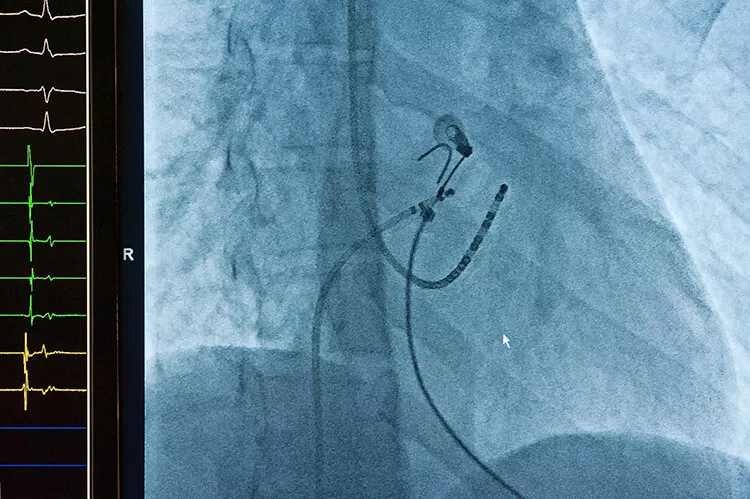

Ilustrační obrázek

Zdroj: Shutterstock